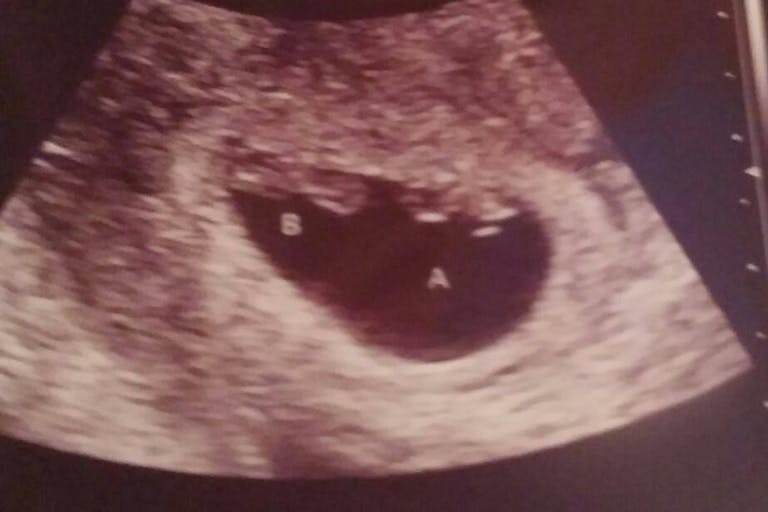

Christina and Shawn were told that their son would die either in the womb, or right after his birth. Since the babies were identical and shared a placenta, if Baby A (with acrania) were to die in the womb, it could cause them to lose both babies, or cause neurological problems for Baby B.